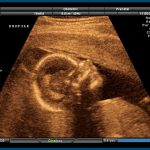

Abortion refers to a voluntary medical procedure that is intended to end the life of a baby in the mother’s womb. There are two primary ways a woman can obtain an abortion.